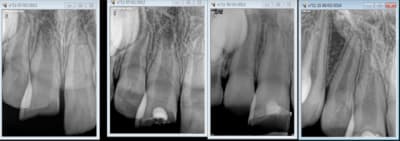

bonjour. Que feriez vous à ma place. Hier, je soigne une jeune patiente de 12 ANS ET 11 MOIS; le bbd n'a pas été fait car la patiente était suivie en odf et pensait que son suivi était fait de fait. A la radio, je suppose que je vais écorner une 47. petite patiente charmante mais qui a très peur; ouvre peu et la dent est encore recouverte par la muqueuse partiellement. Je prends le temps, j'écorne je fais la biopulpotomie et je reconstitue. je constate que la pulpotomie sur dent permanente sur dent immature est devenue un acte NR avec la ccam. Je décide de prendre 50 euros et j'explique à la patiente que cet acte n'est plus remboursé par la secu. Elle ne dit rien part , appelle sa mutuelle entre temps qui me fait passer pour une personne sans scrupule car la mutuelle a expliqué à la patiente que n'ayant pas fait de devis ,elle n'est pas dans l'obligation de me payer et tout et tout... la patiente a rappelé le cabinet un peu en colère visiblement en disant qu'elle avait été mis devant le fait accompli..;je dois dire que je suis stupéfaite, je me suis demenée merci du cadeau. tout de suite après je vais aller m'inscrire à la formation comment éviter le burn out

Premier rdv, tu expliques la situation : La carie est profonde sur une dent jeune avec un nerf volumineux donc je vais tomber dans le nerf et donc afin préserver la vitalité et permettre à la dent de terminer son édification je dois faire "explication du traitement (biodent MTA etc...)" qui n'est pas pris en charge par la sécu.

- Pour une carie profonde, juxta-pulpaire et asymptomatique de dent jeune, le traitement le plus indiqué est le coiffage pulpaire indirect : parois parfaitement propres, fond de dentine affectée, restauration étanche.

- En cas d'exposition, un coiffage pulpaire direct est indiqué : MTA ou Biodentine.

- Une pulpotomie n'est indiquée qu'en cas de symptomatologie "type pulpite irréversible" et en cas d'exposition pulpaire large avec hémostase impossible.

Quel matériau as-tu utilisé pour cette pulpotomie ?

j'ai appris à faire les pulpos au kalsogene(dent de lait et permanente). Cela fonctionne bien.